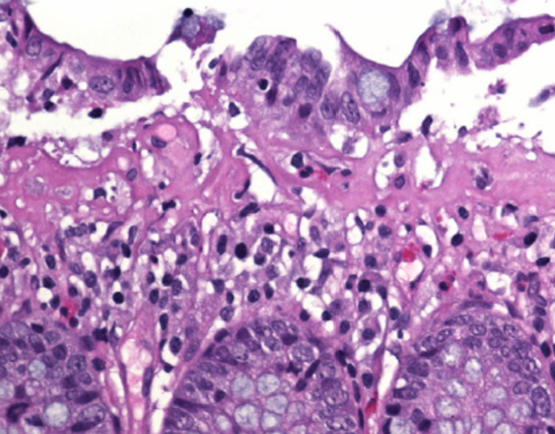

Bedöm biopsin

- Kolonslemhinna med kroniskt och akut inflammatoriskt infiltrat i lamina propria och intraepitelialt. Granulom påvisas. Kryptarkitekturen är oregelbunden.

- Morbus Crohn – granulom ganska specifikt